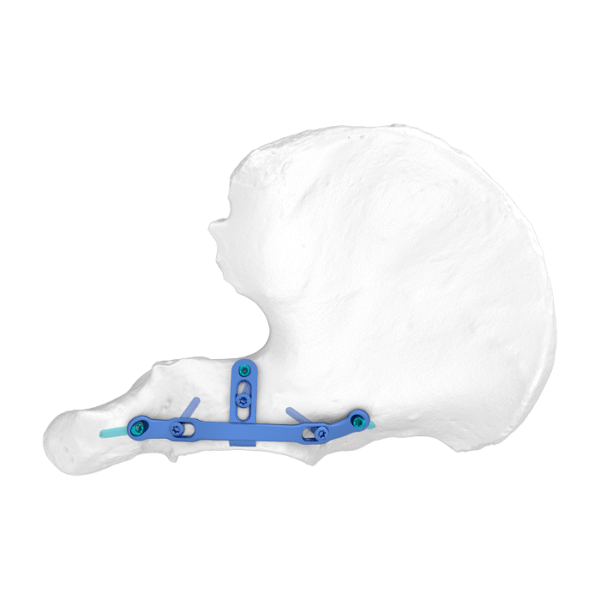

– El diseño curvo asegura una compresión efectiva del borde de fractura.

– El borde afilado permite la compresión directa del hueso a través de la cápsula articular.

– El primer orificio está diseñado como un orificio alargado, conveniente para elegir la posición del tornillo.